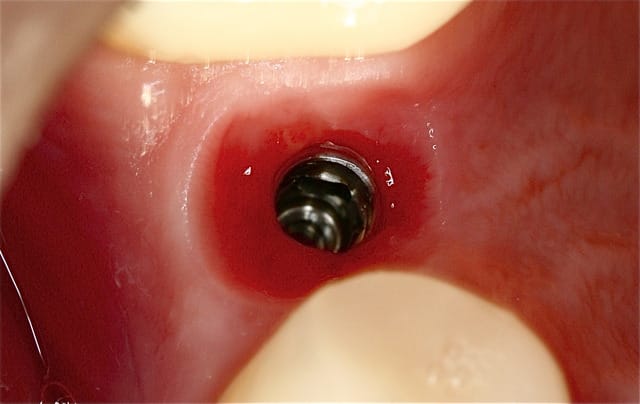

Pour ceux que ca interessent, et parce qu on a m a demandé des cas supplémentaires dans le sujet 23 implants rehabilitation totale, voici un autre cas d implantation immédiate avec la technique minimalement invasive et condensation grace aux forets.

Le patient a reçu un traitement il y a dix ans dans le maxillaire et dans le 4eme quadrant.Comme on peut le voir j´ai du extraire quelques dents au maxillaire: 35 37 et 45.

Le septum de la 37 a été foré avec un foret conique 3 faces.

J ai planté à 60 Ncm sans fracturer le septum.Juste après l opération , les prep caps en zircon ont été cémenté.La restauration définitive 34 jusqu` à 37 été fixé 2 semaines après l implantation avec implantlink (detax). Après un an, le bridge a été retiré facilement pour voir l´état de la gencive et faire une radio de contrôle.On la re ossifiction est satisfaisante et que la gencive "aime" le zircon.

Le bridge a ensuite été recémenté sans correction nécessaire du bridge.